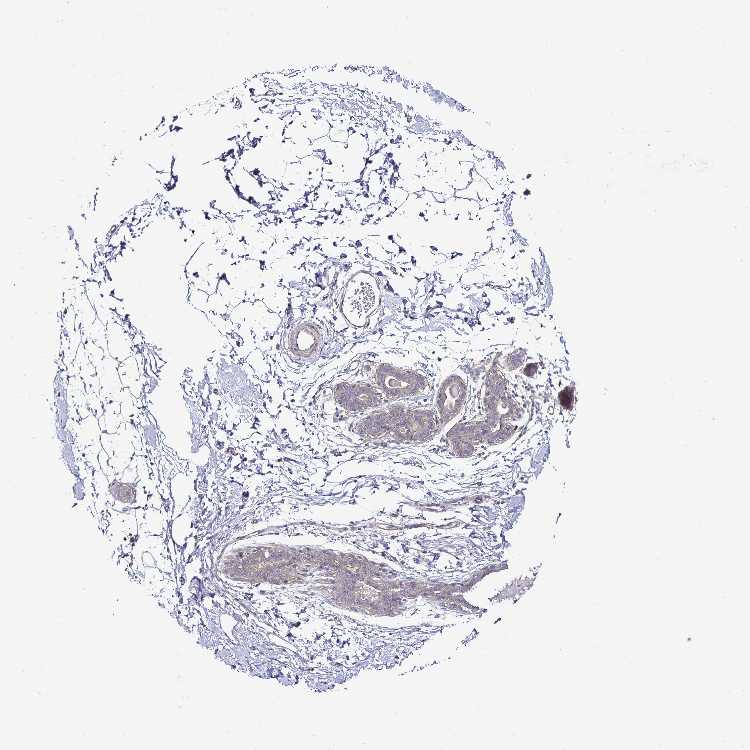

TISSUE PRIMARY DATA BREAST Show tissue menu

BREAST - Antibody stainingi

Antibody staining in the annotated cell types in the current human tissue is reported as not detected, low, medium, or high, based on conventional immunohistochemistry profiling in selected tissues. This score is based on the combination of the staining intensity and fraction of stained cells.

Each image is clickable and will lead to virtual microscopy that enables deeper exploration of all samples and also displays staining intensity scores, fraction scores and subcellular localization as well as patient and tissue information for each sample.

Antibody HPA057790Antibody HPA062208

Adipocytes Not detectedNot detected

Glandular cells Not detectedLow

Myoepithelial cells Not detectedLow